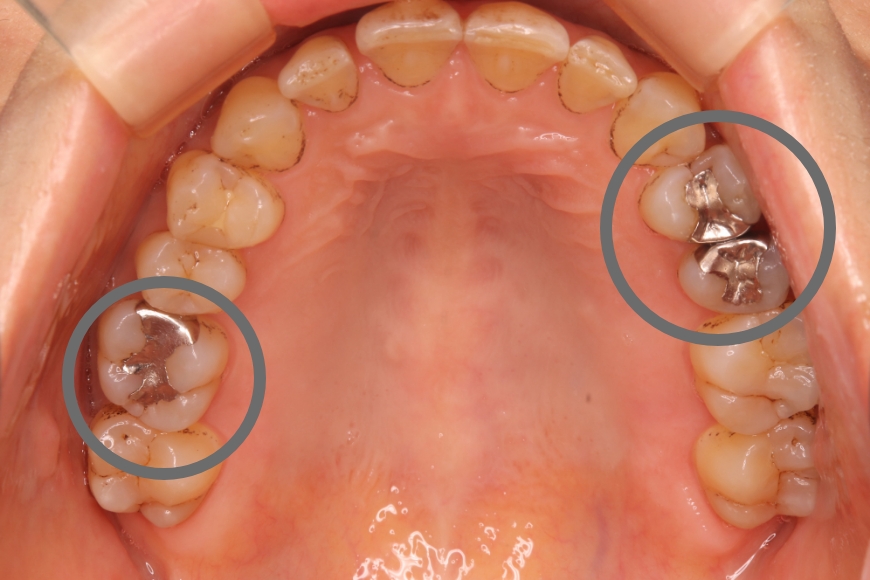

50代女性 左右の奥歯へのインプラント治療

治療内容 下の左右の奥歯が無く、食事がうまくできないことを主訴に来院されました。

左右の奥歯に2本ずつインプラント治療を行いました。奥歯でしっかりと噛めるようになりました。

治療期間・回数 治療期間:約6ヶ月

通院回数:10回程度

治療費用(総額)

1,760,000

(1本440,000円×4本分。時期や手法により異なる場合があります。)